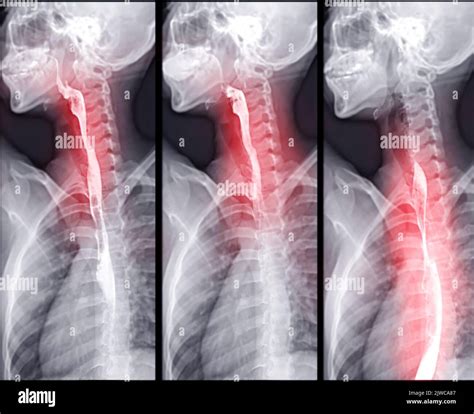

A Video Swallow Study, also known as a modified barium swallow study, is a diagnostic procedure that uses fluoroscopy to observe the swallowing process in real-time. During the study, the patient ingests barium-coated food or liquid, which makes the swallowing structures visible on X-ray images. This allows healthcare professionals to identify any abnormalities or obstructions in the swallowing pathway.

1. Patient Positioning: The patient is positioned in front of a fluoroscopy machine, which captures real-time X-ray images.

2. Barium Administration: The patient is given barium-coated food or liquid to swallow. The barium makes the swallowing structures visible on the X-ray.

3. Swallowing Observation: The healthcare provider observes the swallowing process on a monitor, noting any abnormalities or obstructions.

4. Data Collection: The fluoroscopy images are recorded for detailed analysis and documentation.

Interpreting the results of a Video Swallow Study involves analyzing the fluoroscopy images to identify any abnormalities in the swallowing process. Key areas of focus include:

• Oral Phase: The movement of the tongue and the coordination of the oral muscles.

• Pharyngeal Phase: The movement of the bolus (food or liquid) through the pharynx and the coordination of the pharyngeal muscles.

• Esophageal Phase: The movement of the bolus through the esophagus and into the stomach.